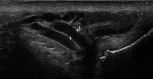

Fig. 1

Varicocele in B-mode presentation (1= 0.34 cm)